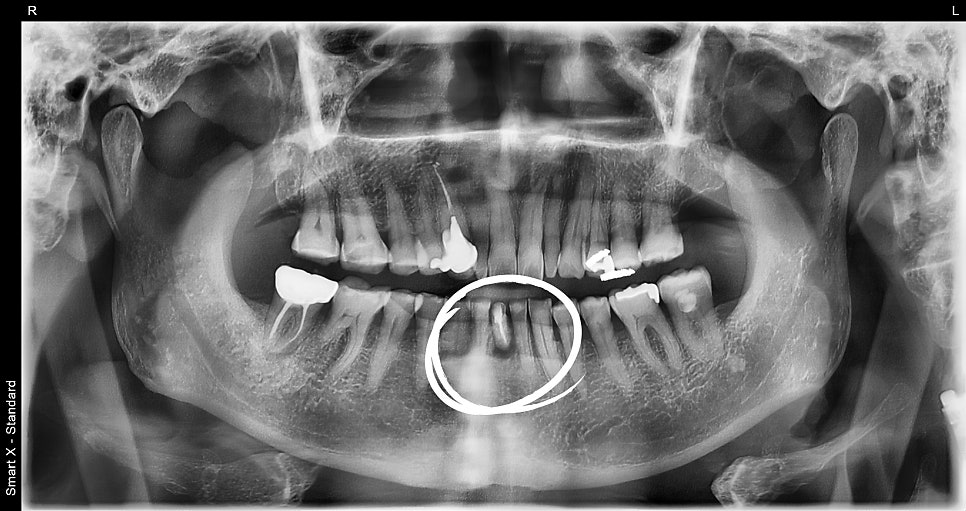

내원 당시 초진 엑스레이 사진

환자분은 아래 앞니가 심하게 흔들린다는 주호소로 내원하셨고,

파노라마 엑스레이 촬영 결과 자연치 보존이 불가능한 상태였습니다.